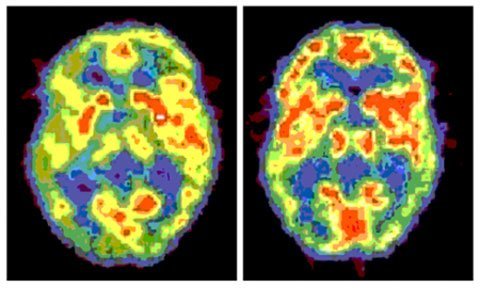

Bộ não được phân chia thành 2 bán cầu đối xưng. Dù hoạt động cùng nhau nhưng não trái thiên về suy nghĩ mang tính phân tích và lý trí hơn, trong khi não phải phụ trách suy nghĩ theo hướng thị giác và khái niệm. Hai bán cầu não cũng hoạt động theo cách đối ngược, ví dụ như bạn bị vấp ngón chân trái thì cơn đau sẽ do bán cầu não phải “xử lý”. Và chúng sẽ đưa “phần đúng hướng lên trên” đối với bất kỳ thứ gì bị lộn ngược, ví dụ như các hình ảnh tri nhận qua mắt bạn thực tế bị lộn ngược và bộ não đã chỉnh sửa nó về đúng tư thế. Tuy nhiên, điều kỳ dị nhất ở đây là: ngay cả khi bị mất một nửa bộ não, con người vẫn có thể sống sót mà không cần có nó.